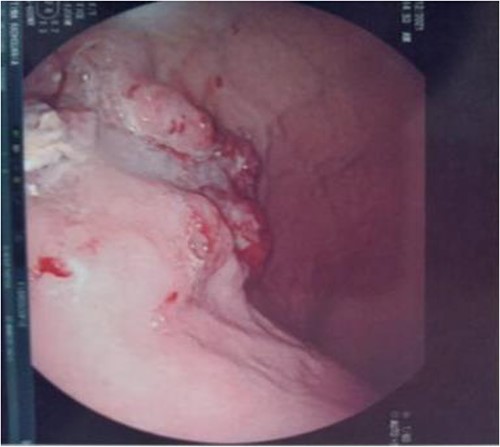

Serum carcinoembryonic antigen was 4.3 μg/L (normal value <5.1 μg/L). Biological tests showed normal platelet count and prothrombin time was 70%. Hemoglobin level was 12.2 g/dL. His biochemical tests showed hypoalbuminemia (31 g/dl). The patient was scheduled for a colonoscopy. However, a large bowel obstruction occurred during the bowel preparation. Thus, computed tomography (CT) scan of the abdomen and the pelvis was performed revealing circumferential wall thickening narrowing the rectal lumen and invading the prostate and the mesorectum with upstream bowel dilatation without extrinsic mass, lymphadenopathy, or metastasis. The patient underwent colostomy without incident. Colonoscopy was performed after colostomy, showing large, circumferential, infiltrative, friable, and stenosing submucosal mass with erythematous overlying rectal epithelium, taking on the appearance of grape clusters (shown in Fig. 1). Mucosal biopsies showed invasive poorly differentiated carcinoma referring at first a neuroendocrine tumor. Second mucosal biopsies were performed showing inflammatory modifications of the rectal mucosa without any malignancy. Third mucosal biopsies concluded to poorly differentiated carcinoma. Magnetic resonance imaging (MRI) of the pelvis showed circumferential wall thickening narrowing the rectal lumen and invading posterior peripheral area of the prostate, the bladder, the left seminal vesicle, and the mesorectum (shown in Fig. 2). The radiologist suggest a rectal cancer (RC) invading the urogenital tract or a PC invading the rectum subject to non-injected MRI. In fact, the MRI was interrupted before gadolinium injection because the patient was claustrophobic. Serum prostate specific antigen (PSA) was then ordered and it was raised at 25.59 μg/L (normal value<4 μg/L). Therefore, macro-biopsies of the rectal mucosa using snare loop were performed showing a poorly differentiated infiltrative carcinoma and immunohistochemical (IHC) stains were strongly positive for PSA and pancytokeratin and negative for anti-CD56 (shown in Fig. 3). Then, a clear diagnosis of PC invading the rectum was established. Bone scintigraphy was performed and was normal. The patient was referred to urology department. He underwent surgical castration. Then, androgen depletion therapy (ADT) was started. A total of 3 months later, there was a good response with his PSA level dropping to 0.5 μg/L. About 3 years after, patient is still alive, but PSA level has increased to 52 μg/L. The CT scan of the thorax, the abdomen, and the pelvis showed a prostatic hypertrophy with loss of the security edging with the rectum without any metastatic involvement.

Large, circumferential, infiltrative, friable submucosal mass with erythematous overlying rectal epithelium, taking on the appearance of grape clusters.